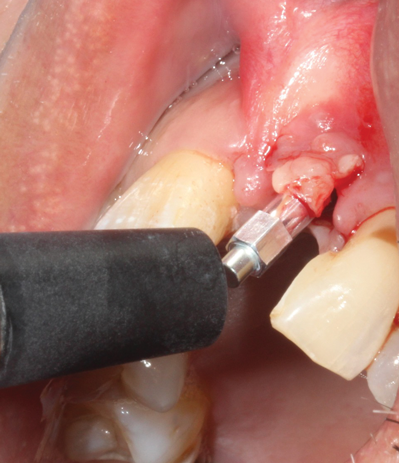

(39.) The composite tooth shell was modified to fit around the abutment, positioned intraorally, and bonded to the abutment with flowable composite in the incisal half.

Figure 39

(42.) The remaining portion of the titanium abutment was cut off, and the palatal aspect was undercontoured.

Figure 42